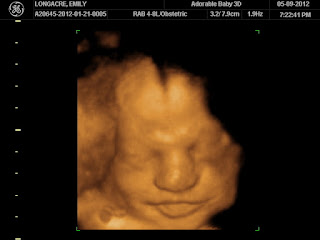

Here are some pics of LB from his 3D/4D ultrasounds. I was thinking that 31 weeks would be the last one but now I'm thinking I want to go one more time before he gets here. I just love seeing his little face!!!

31 Weeks

He really has changed a lot! I can't wait to meet him!!!